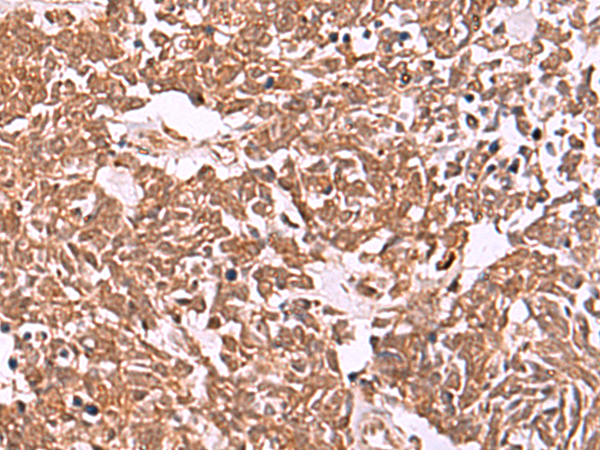

IHC positive control:

Human lung cancer and Human esophagus cancer

IHC Recommend dilution:

30-150